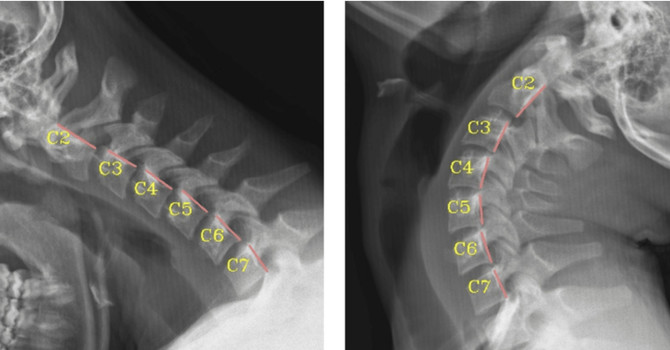

• Radiographic Sagittal Alignment and Neurological Changes Following Conservative Cervical Rehab

• Retrospective Cross-Sectional Analysis of Abnormal Cervical Mechanics with Scoliosis

• Radiographic Sagittal Alignment and Kinetic Chain Alterations in Geriatric Patients with Scoliosis: A Case Series